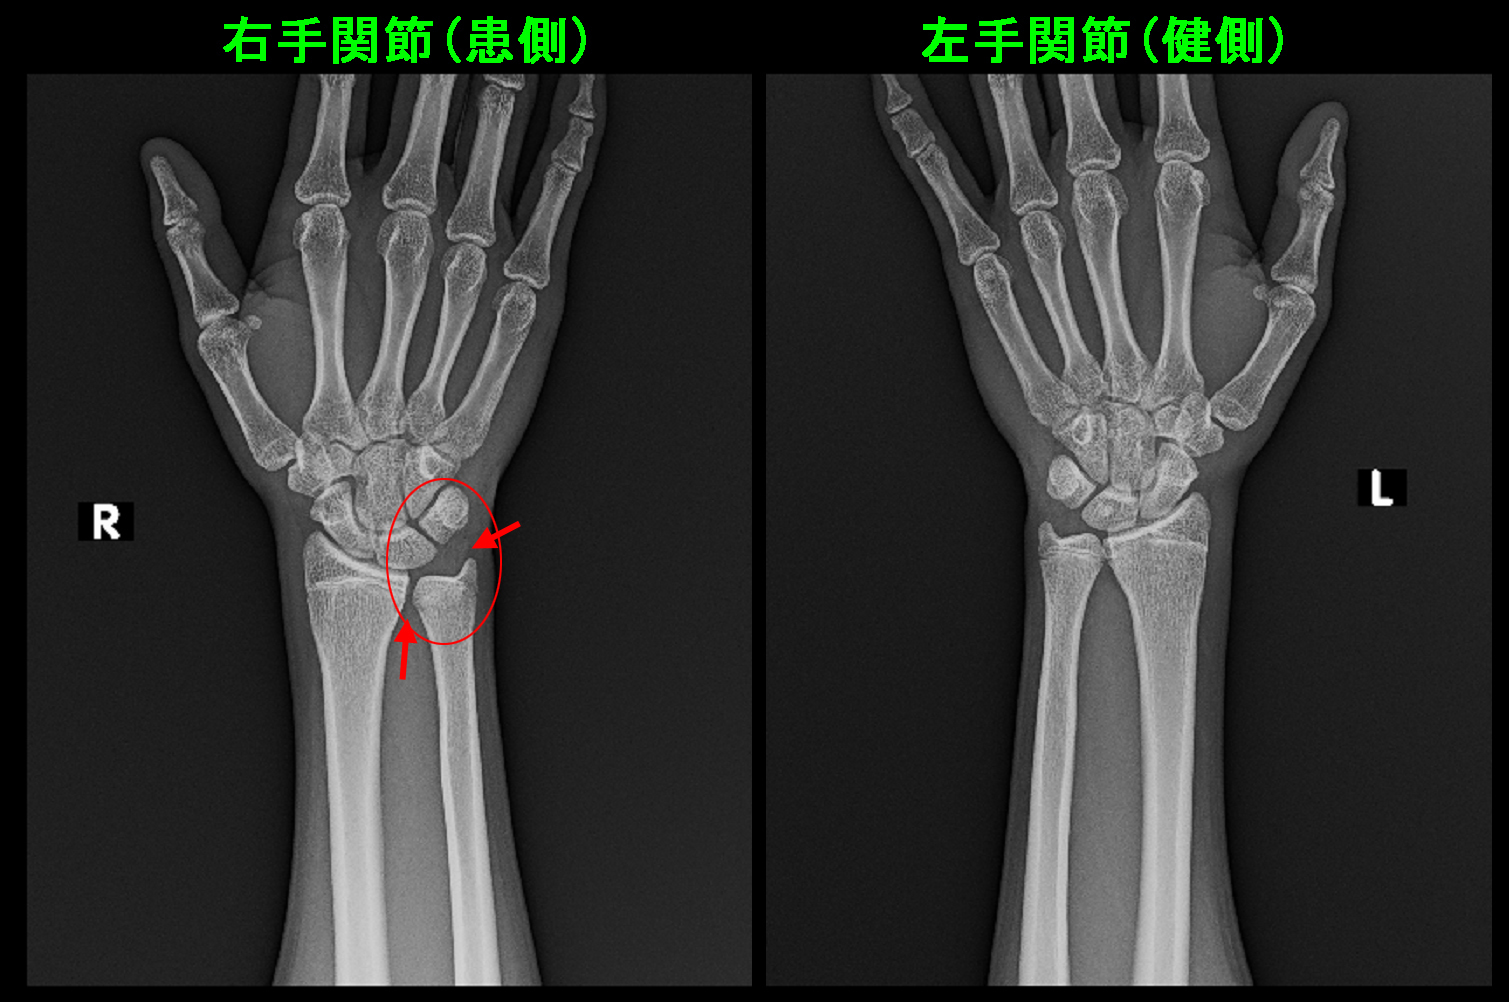

15才男 MR1.jpg

左手関節の三角線維軟骨は正常で黒く描出されていますが(青矢印)、右手関節の三角線維軟骨は一部が白くなっており(赤矢印)、炎症所見を示します。炎症とは小さく傷ついた状態と理解して良いと思います。

服薬で軽減しなかったので、より効果が期待できる手関節内注射の治療を施行しました。この際に特に処方はしていません。

15才男 Xp造影.jpg